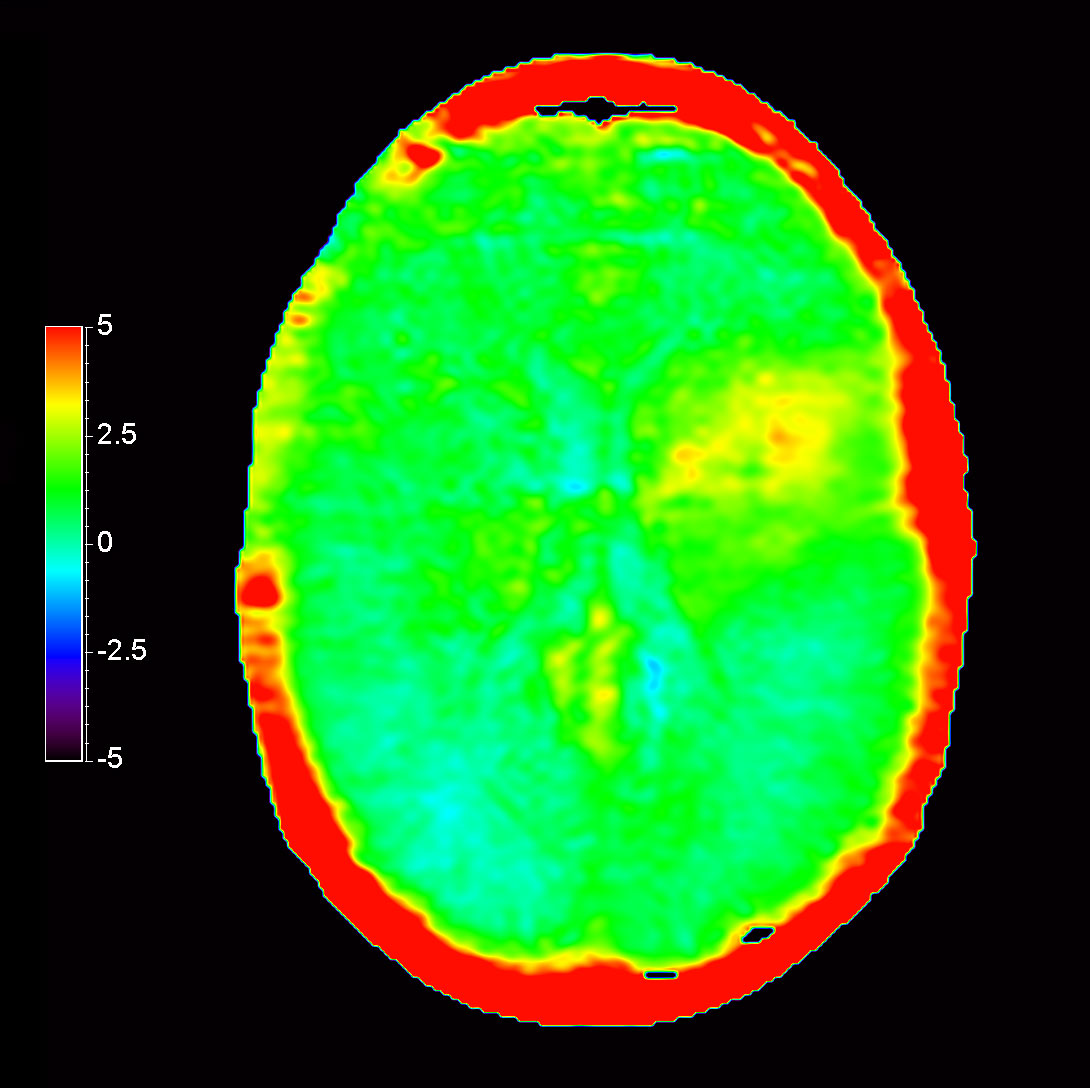

Axial 3D APT

-